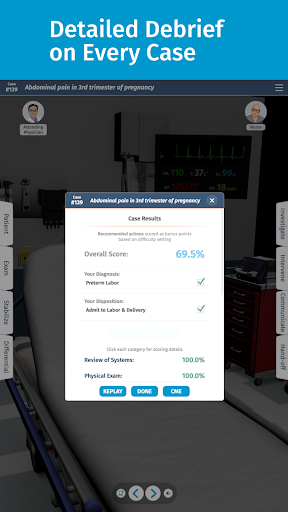

• Điểm số chi tiết và phân tích toàn bộ trường hợp - tìm hiểu điểm mạnh và điểm yếu của bạn

Các trường hợp có thể lặp lại vô hạn của Full Code đo lường các kỹ năng trong cả chẩn đoán và quản lý, cho phép bạn học hỏi từ những sai lầm của mình trong một môi trường không có rủi ro. Xây dựng năng lực để bạn có thể đối mặt với các trường hợp thực tế phức tạp một cách tự tin.